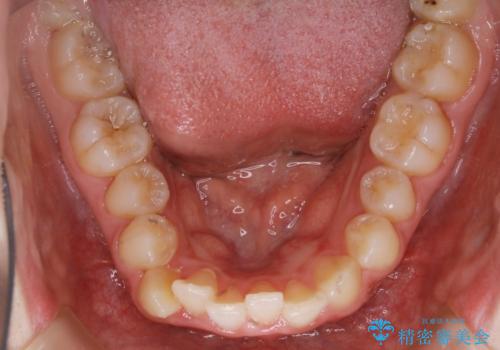

【非抜歯】すきっ歯と噛み合わせの治療

- 上の前歯のすきっ歯と下の前歯のガタつきを主訴にご来院されました。

噛み合わせの改善も同時に進めつつ、主訴の部分も効率的に治していくためマウスピース装置でゴムかけを行いながら治療を進めていきました。